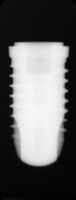

Thommen

SPI Element

Connection Interface

External interfaceInternal interface

Body Shape

Non-tapered bodyTapered apex

Thread Design

ThreadedV-shaped threads

Additional Features

Apical groovesCurved apeximplantStraight flangeWider flange